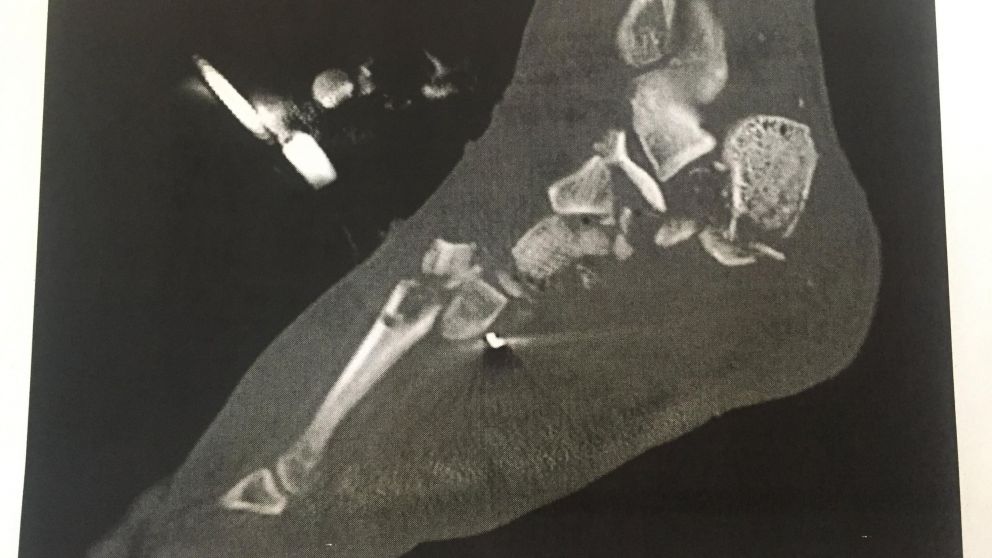

Un usuario de la red social Reddit ha dejado en shock a miles de personas con sus imágenes documentando un almuerzo un tanto peculiar. Según el usuario Incredibly Shiny Shart, su pie tuvo que ser amputado debido a un accidente de motocicleta, pero cuando esto sucedió le pidió a los doctores que si se podía quedar con la extremidad, a lo cual ellos accedieron, reseña PijamaSurf.